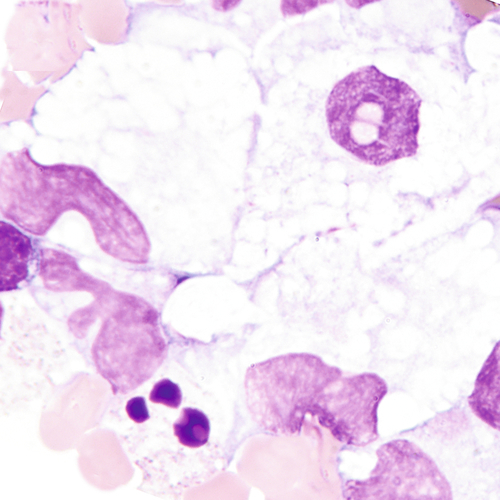

Intact neutrophil with engulfed homogeneous mass. The mass displaces the nucleus of the neutrophil and is composed of degenerated nuclear material. Lupus erythematosus (LE) cells are formed in vivo and in vitro in serous fluids. LE cells may also form in synovial fluids.

Lupus erythematosus